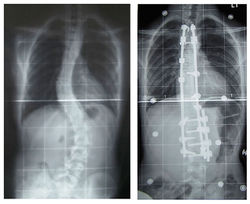

Лечение идиопатического сколиоза зависит от тяжести искривления позвоночника, потенциала спинного хребта для дальнейшего роста и риска того, что кривизна будет прогрессировать. Сколиоз первой степени (менее 30 градусов отклонения) можно контролировать и лечить с помощью упражнений. Умеренно тяжелый сколиоз (30-45 градусов) у ребенка, можно исправить с помощью корсета. Тяжелые искривления, которые быстро прогрессируют нужно лечить хирургическим путем с размещением металлических конструкций в позвоночном столбе. Во всех случаях раннее вмешательство обеспечивает наилучшие результаты. Растущий объем научных исследований свидетельствует об эффективности применения специализированных лечебных программ физической терапии, которые включают в себя общеукрепляющие.[5][6][7][8]

Хирургическое лечение сколиоза у детей[править | править код]

Хирургическое лечение детей с прогрессирующим сколиозом в возрасте до 10 лет, чрезвычайно сложная мировая проблема хирургии позвоночника т.к. в этом возрасте структуры позвоночника до конца не сформированы и рост позвоночника не завершен. В связи с чем, применение техники операций как у взрослых или подростков приводит к ограничению роста позвоночника.

Схема №1 (часто используется в Америке и Европе). Этапное хирургическое лечение – выполняют оперативную коррекцию конструкцией, затем данную конструкцию удлиняют каждые 1-2 года, до 14-15 лет и затем выполняют установку стабильной конструкции.

Схема №2. Одномоментная коррекция с применением стабильной конструкции (в настоящее время, не рекомендуется применять). Выполнять сразу операцию с установкой стабильной конструкции, чревато тяжелым осложнением – синдромом “коленчатого вала” когда сколиоз продолжает прогрессировать с уже установленной конструкций на позвоночнике.

Схема № 3. Выжидательная тактика (часто встречается в России)- ребенка наблюдают, выполняют консервативное лечение до возраста 16-17 лет (завершения роста позвоночника) и затем выполняют операцию с использованием статической конструкции

Применение выжидательной тактики приводит к формированию тяжелейшего сколиоза к 16-17 годам, который очень трудно поддается коррекции. Также, формируются изменения со стороны сердца и легких. Часто пациенты обращаются с настолько тяжелой формой сколиоза при котором выполнить операцию невозможно.[21]